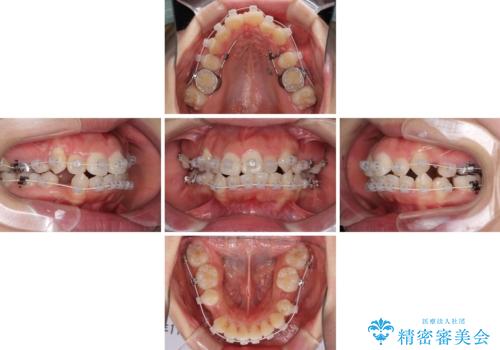

- 矯正装置

- 審美装置

咬み合わせの乱れが著しく、治療途中で一部反対咬合となってしまいました。

アンカーなどをうまく使用して、3年の期間を要してきれいに仕上げることができました。